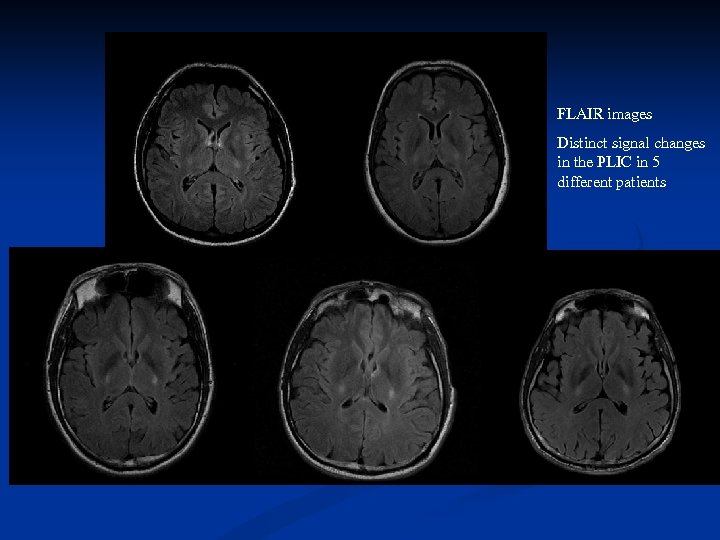

FLAIR images Distinct signal changes in the PLIC in 5 different patients

FLAIR images Distinct signal changes in the PLIC in 5 different patients